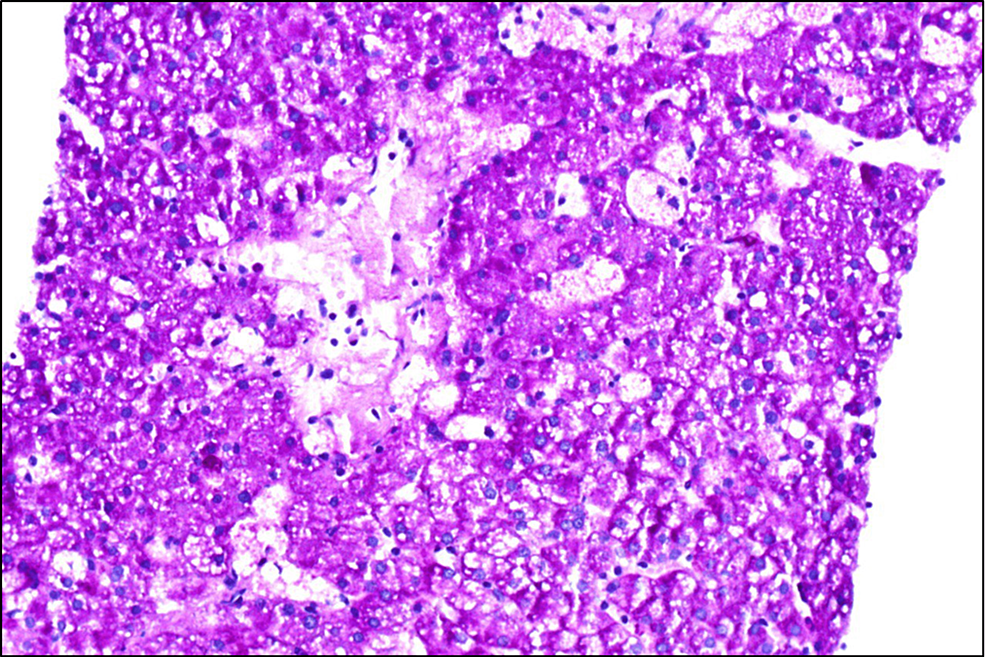

NiemannPick disease. Light micrograph of a section through bone marrow Pick Disease On Mri What is to be understood by the term pick’s disease? Diagnosis may include blood tests, mri and eeg scans, and sometimes a lumbar puncture. This article is a brief review of the clinical, radiographic, and pathologic features of pick disease. Identify the etiology and epidemiology of pick disease. Is this a clinical syndrome (s) of frontotemporal lobar atrophy, or a. Pick Disease On Mri.

NiemannPick disease, light micrograph Stock Image C015/7131 Pick Disease On Mri Pick disease (named after arnold pick) is a progressive dementia defined by clinical and pathologic criteria. Frontotemporal lobar degeneration (ftld) is the pathological description of a group of neurodegenerative disorders characterized by focal atrophy of the frontal and/or. Review the appropriate history, physical, and evaluation of pick disease. Is this a clinical syndrome (s) of frontotemporal lobar atrophy, or a. Pick Disease On Mri.

NiemannPick disease Pick Disease On Mri Pick disease (named after arnold pick) is a progressive dementia defined by clinical and pathologic criteria. What is to be understood by the term pick’s disease? Identify the etiology and epidemiology of pick disease. This article is a brief review of the clinical, radiographic, and pathologic features of pick disease. Pick’s disease is a specific type of frontotemporal dementia, a. Pick Disease On Mri.